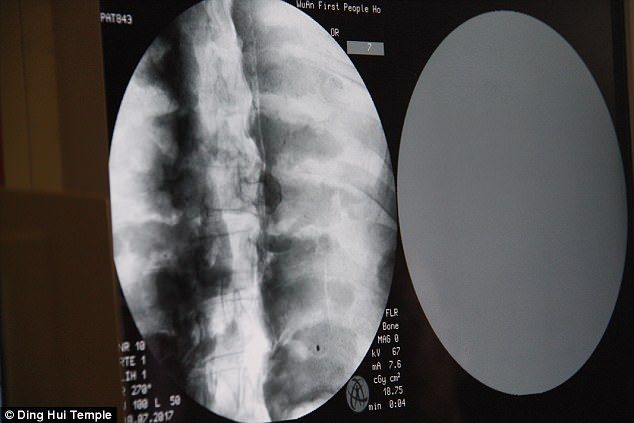

研究學者用X光還有CT掃描檢驗這座高僧坐像,有了驚人的發現:他不但保有完整的骨頭,竟然連大腦都還在,武永慶醫生在受訪時表示:“我們在掃描後發現,他的骨頭跟一般人的一樣完整。”

“上額、上面的牙齒、肋骨、脊椎骨、連關節全部都在,真的是很令人驚奇的情況。”